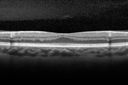

Plaquenil Toxicity - Bull's Eye Maculopathy - 25 Years Therapy OCT Line Scan942 views73-year-old woman has been on Plaquenil for twenty five years. Plaquenil has now been stopped for 6 months. VA continues to decline as does visual function - 20/80 OD , 20/40 OS